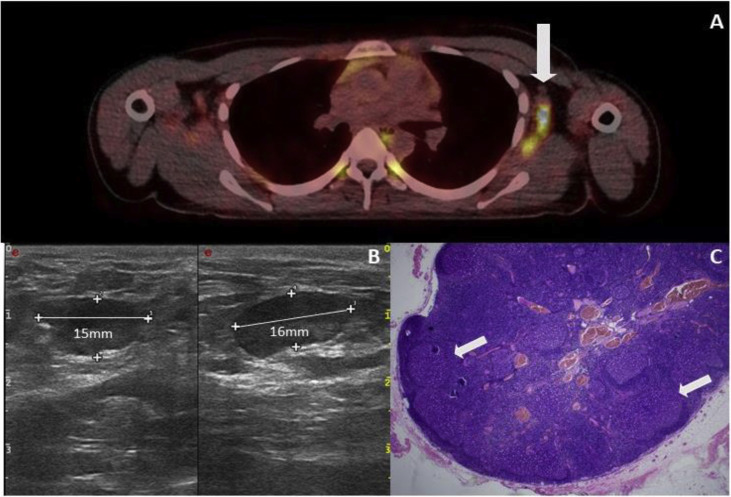

A 27-year-old female patient had an initial diagnosis of a 0.4-mm-thick melanoma on the left scapula in September 2020, followed by removal of a melanoma in situ on the left lower leg in January 2021. On 29th March 2021, the first vaccination with BioNTech's vaccine took place. On 15th April 2021, an FDG PET/CT scan ordered by the primary care physician showed highly malignant lymph nodes in the left axilla (Fig. 3 A). One week later, the patient presented to our clinic for the first time. A lymph node ultrasound was performed, which showed multiple lymph nodes, some of which were echo-deficient, with increased marginal vascularisation and a maximum diameter of 1.6 cm in the left axilla, so there was a high suspicion of lymph node metastases (Fig. 3B). Together with the patient, the performance of a diagnostic lymph node removal was determined. A total of four intraoperatively conspicuous lymph nodes were removed from the left axilla. Histopathologically, there was no evidence of infiltration by melanoma but marked lymphofollicular hyperplasia in all lymph nodes (Fig. 3C). The patient's postoperative clinical course was without complications.

Fig. 3.

Case 1. (A) PET-CT examination of the patient, which shows a pronounced FDG accumulation in the area of the lymph nodes of the left axilla (

). (B) Lymph node ultrasound shows pronounced enlargement with a clear decrease in echogenicity. (C) Histological picture of the lymph node showing follicular hyperplasia (

). Metastases from the melanoma cannot be seen (HE).